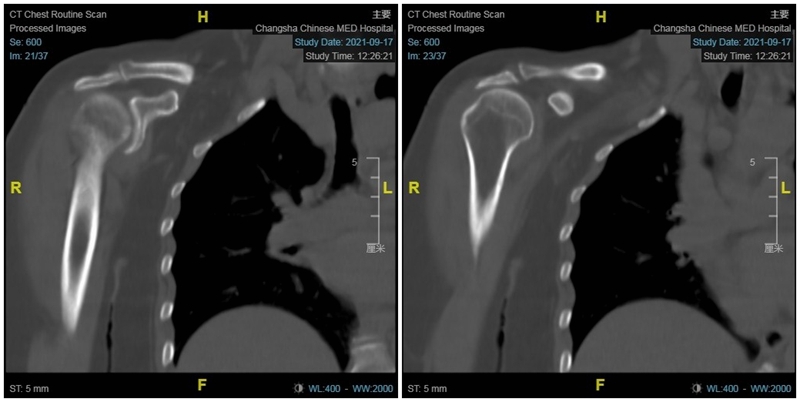

术前影像学检查示肱骨头向上移位,关节盂、肩峰和肱骨头退行性改变,典型肩袖撕裂性骨关节病(CTA)改变。